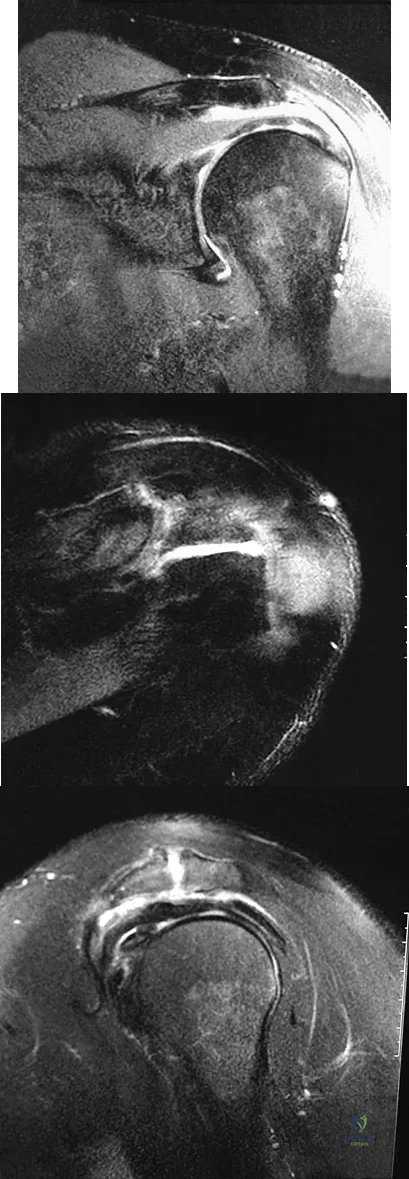

Figures 26a through 26c show the MRI scans of a 47-year-old man who underwent arthroscopic shoulder surgery 6 months ago and continues to have pain despite a prolonged course of rehabilitation. Management should now consist of

Explanation